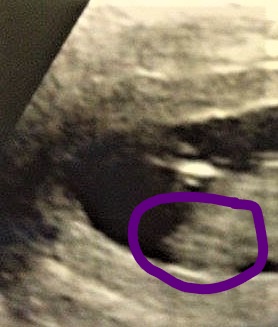

Also a slight girly lean, but since there is something on top of the nub that could be stacking, I'm not completely sure of the girly guess.

This is the nub. There is a little bump on top which could mean boy. The bump could also be unrelated to the nub, so this is a tricky one.

Attachment 34830